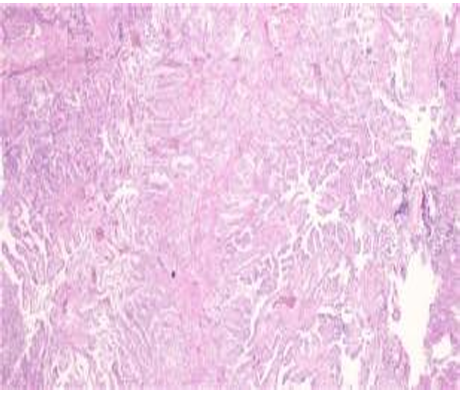

(4脑室占位)送检组织呈乳头状增生被覆立方柱状上皮,未见显著坏死及细胞异型,核分裂,符合脉络丛乳头状瘤。

免疫组化染色结果: <第1次>E(4脑室占位常规):Ki-67(+,5%)、P53(野生型)、SMARCA4(未缺失)、GFAP(局灶+)、S-100(+ )、Vimentin(+)、CK20(-)、CK7(-)、EMA(-)、IDH 1(未突变)。

<第2次>E(4脑室占位常规):SYN(+)。